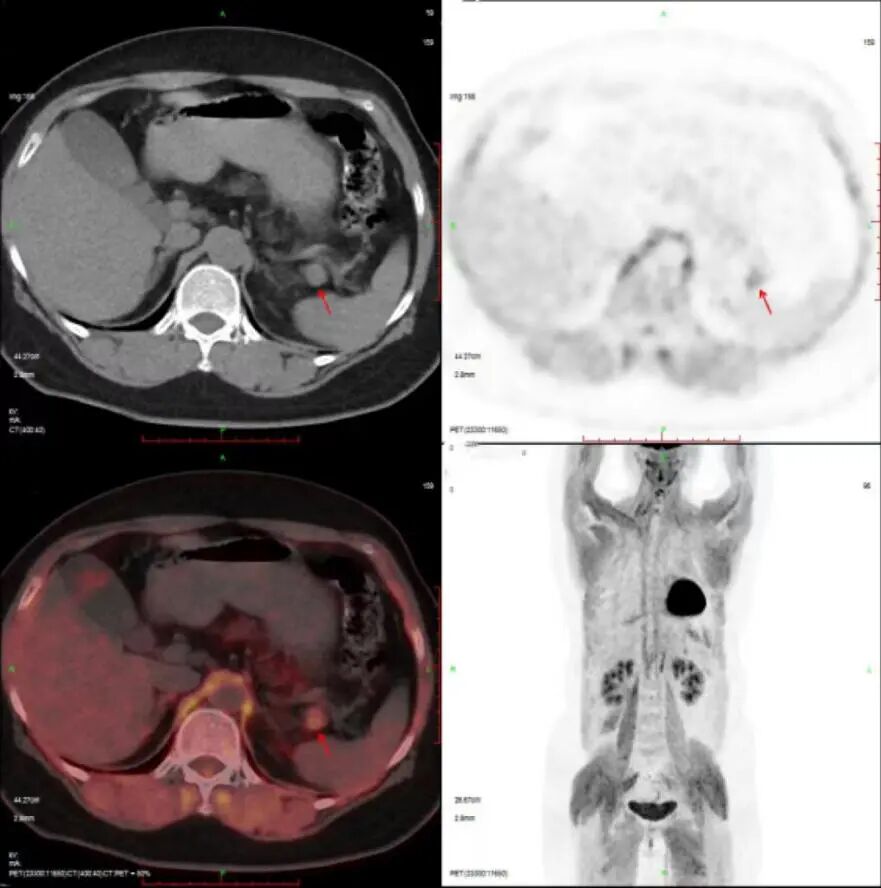

王阿姨PET/CT检查图像如下:

可从图像明显看出胰腺尾部高代谢结节,

结合王阿姨的其他化验、检查结果

考虑功能性胰岛细胞瘤(胰岛素瘤)